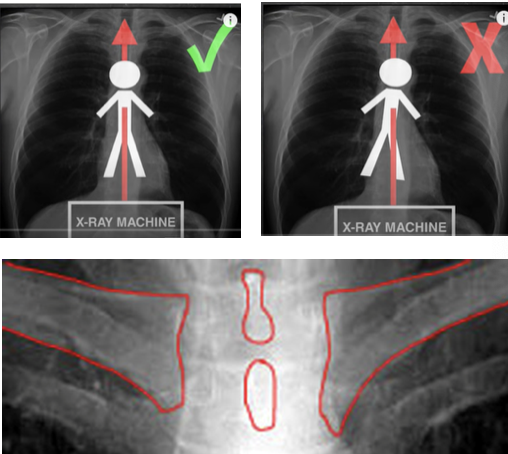

how is an AP X-ray taken?

-plate is placed behind the person

-xray is taken from the front causing the heart to appear larger than on the PA

how is a PA xray taken?

-plate is placed in front of the person

-xray is taken from behind, this then hits the heart slightly later

are most x rays PA or AP?

PA

- the person is asked to move their arms to take their scapula away from the lung fields to make it easier to read

how do you assess for rotation on chest xray?

-the space between the medial clavicle and the margin of the adjacent vertebrae should be equal to each other